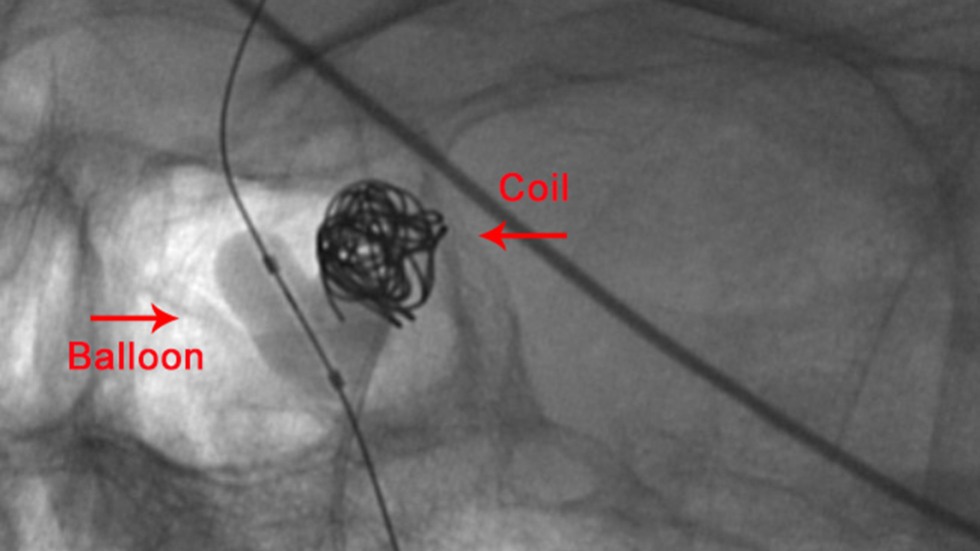

Balloon-Assisted Coiling

Balloon Assisted Coiling: Balloon-assisted coiling is used to treat wide-necked (opening too large to keep the coil in place), complex-shaped cerebral aneurysms.